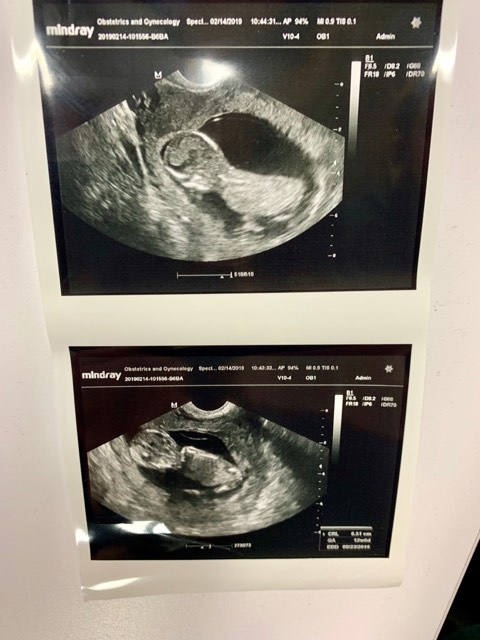

12 weeks and 4 days! We were thrilled to see our little peanut dance around and make a fist at us during our ultrasound! Nuchal screening came back normal, we are on track for 08/17/19 🙏❤